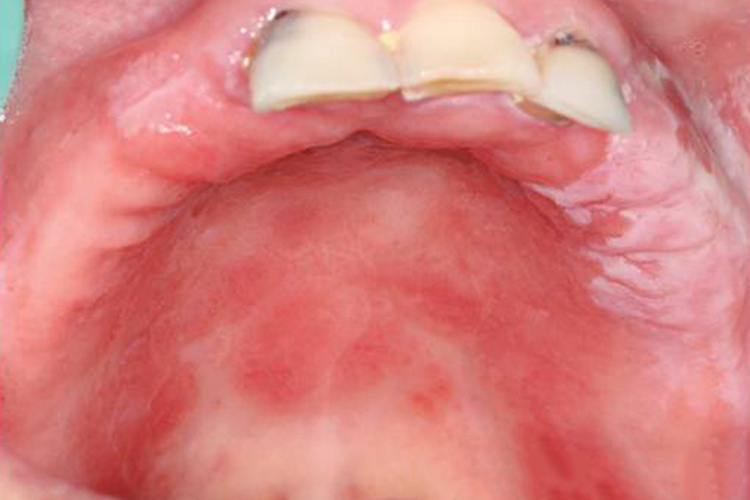

义齿性口炎患者可见义齿接触区域有红斑和水肿,患者常伴有黏膜灼痛和口干等症状。

义齿性口炎损害部位常在上义齿腭侧面接触的腭、龈黏膜。义齿承托区黏膜充血,呈点状或片状红斑和水肿,严重者伴有颗粒或乳头样增生。义齿性口炎大多无明显自觉不适,少数患者有黏膜灼痛和口干等症状。